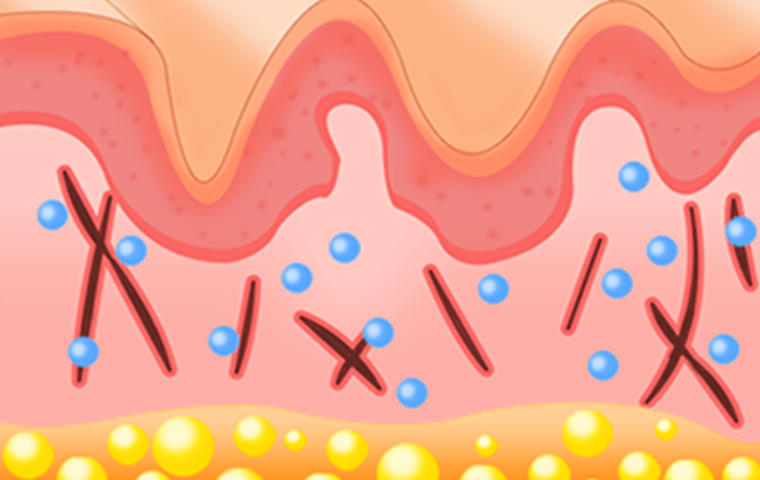

PLA성분이 분해되면서 콜라겐 등의

신생조직 생성을 촉진합니다.

약 6주 후부터

피부 복원 효과를 확인하실 수 있습니다.